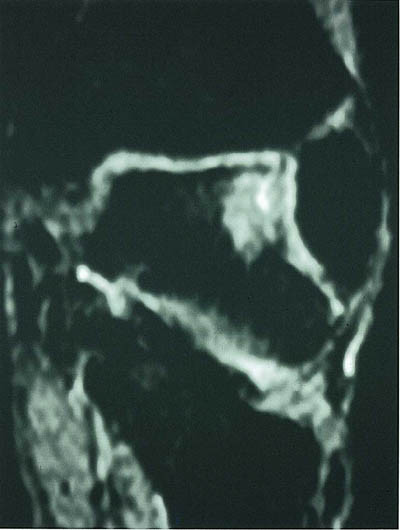

Mesteparten av sinus tarsi er fylt med fett. Dette gir høysignal på T1-vektet sekvensog lavsignal på fettsuppresjonssekvenser. Blodkar og nervefibrer gir små punktformige lavsignaler medialt i fettvevet på T1-vektet sekvens. Ligamentene gir lavsignal på spinnekkosekvensene. Figur 1 viser en normal sinus tarsi. I koronalplanet sees ligamentum cervicale ventralt og ligamentum interosseus noe lenger dorsalt. Det mest fremtredende og hyppigste MR-funnet ved sinus tarsi-syndrom er lavsignalområder på T1-vektet sekvens og lav- eller høysignalområder på T2-vektet sekvens. Forandringene er forårsaket av fibrose (fig 2) med eller uten inflammasjon (fig 3). Av og til kan vi se små væskelokulamenter som representerer ganglioncyster (fig 4). Ligamentene kan være vanskelig å se, enten fordi det er mye inflammasjon eller fordi de er røket. Hos en del pasienter kan man finne ruptur av laterale ankelligamenter, spesielt ligamentum talofibulare anterior.